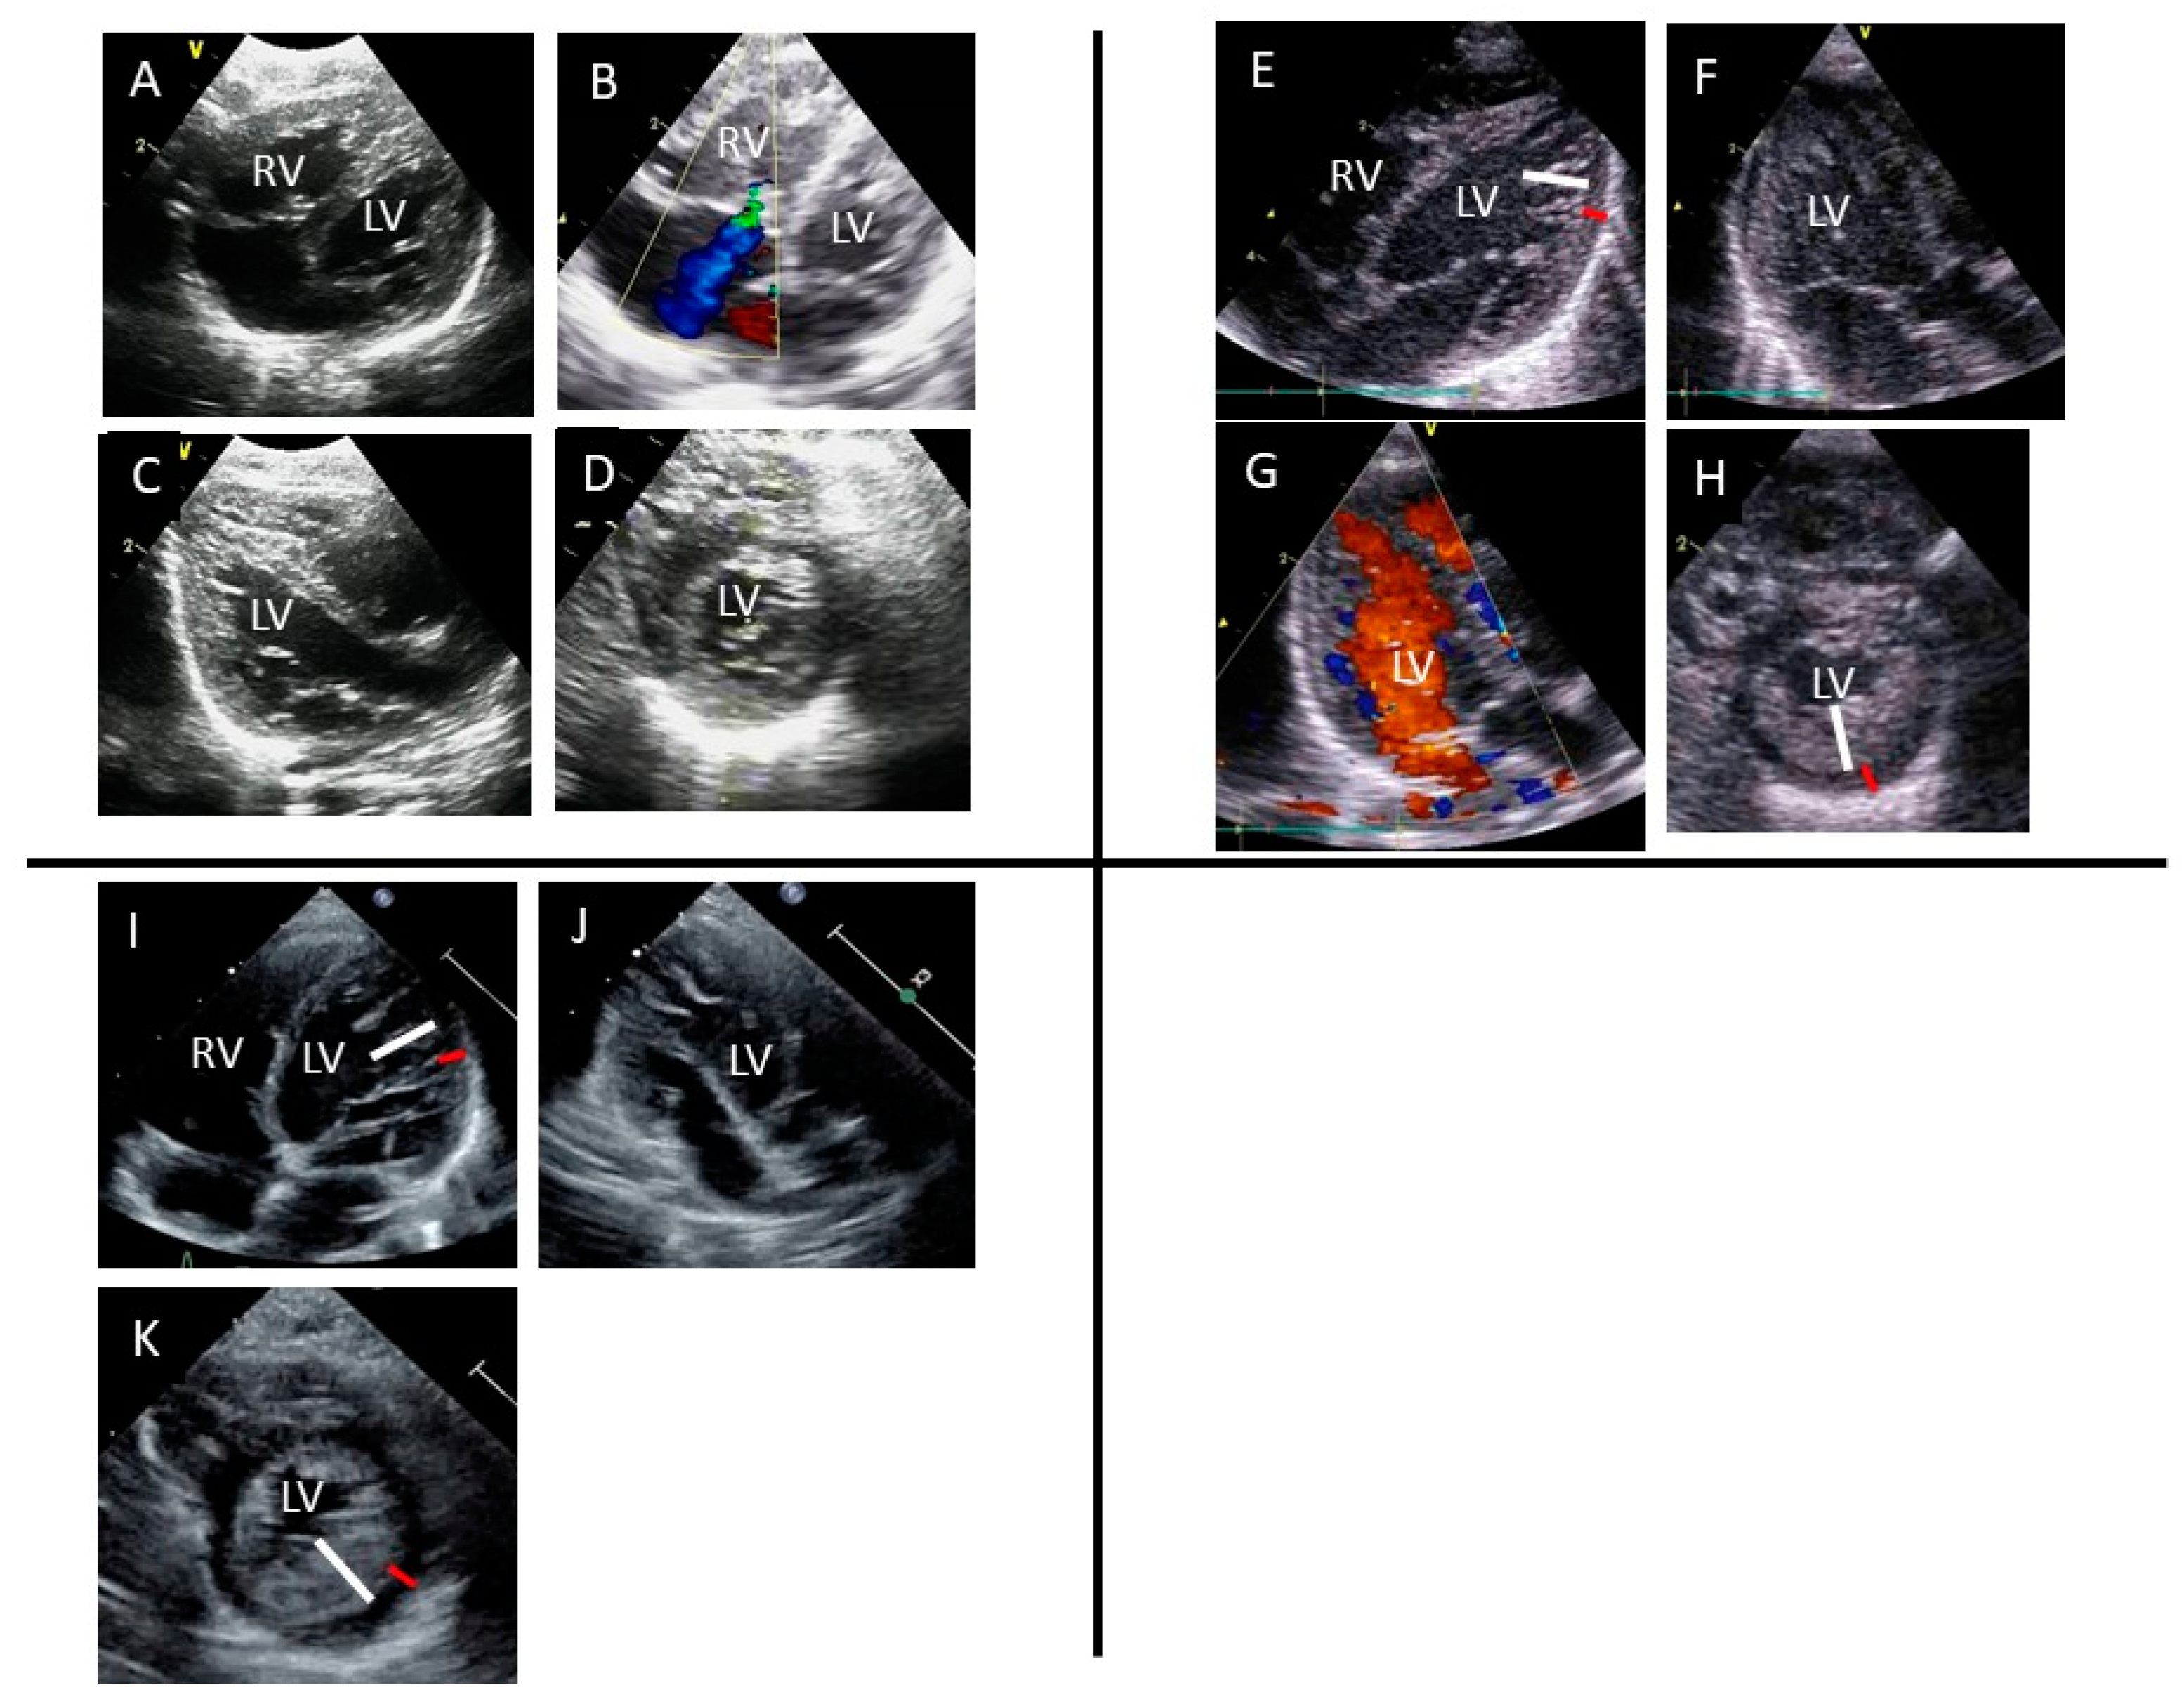

Furthermore, echocardiography revealed a normal LV ejection fraction (56%) and LVH (the Z-scores of interventricular septum and LV posterior wall thickness were 1.03 and 2.60, respectively), moderate tricuspid regurgitation, and pulmonary hypertension (Figure 1). Other extracardiac malformations were not observed. The patient was diagnosed with pulmonary hypertension and tricuspid valve regurgitation secondary to neonatal asphyxia and LVH secondary to GDM. Oxygenation was performed, which improved breathing. However, oral nutrition was inadequate, and heart failure was suspected. Although pulmonary hypertension and tricuspid regurgitation had improved 1 week after delivery, substantial trabeculations in the LV were noticeable instead of LVH, suggesting LVNC with reduced LV contraction (LVEF of 41%) (Figure 1). The patient’s symptoms gradually improved, and he was discharged 22 days after birth. LVNC still persisted at 1 year old (Figure 1).

Figure 1. An ultrasound image showing an abnormal, highly trabeculated left ventricular myocardium (AK): four-chamber (A,B), long-axis (C), and short-axis (D) views showing LVH at birth. B demonstrates moderate tricuspid regurgitation (blue flow) due to pulmonary hypertension; four-chamber (E), long-axis (F,G), and short-axis (H) views 7 days after birth. E and H demonstrate compacted layer (red line) and noncompacted layer (white line). Noncompacted layer shows deep intertrabecular recesses connecting to the LV cavity. G demonstrate red blood flow enter into deep intertrabecular recesses; four-chamber (I), long-axis (J), and short-axis (K) views at 1 year old. Similarly, I and K demonstrate compacted layer (red line) and noncompacted layer (white line). LV, left ventricle; RV, right ventricle.